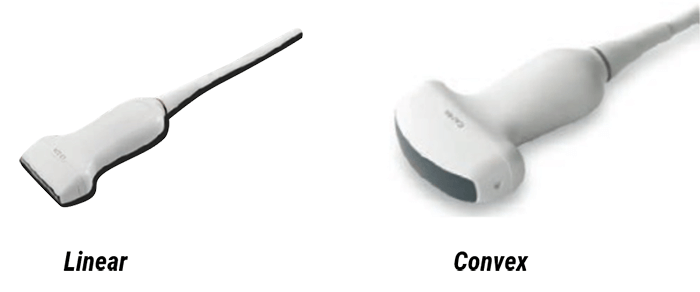

- The Linear transducer where the crystals are arranged in linear form, the shape of the beam is rectangular with a good resolution. This type of transducers is used for different applications such as vascular, blood vessels, breast, thyroid, and tendon examination. It is also used in the measurement of body fat and musculus thickness for daily health care checks

- The Convex transducer is characterized by the curvilinear arrangement of the crystals. It is used for abdominal examinations, transvaginal and transrectal examinations, and Gynecology